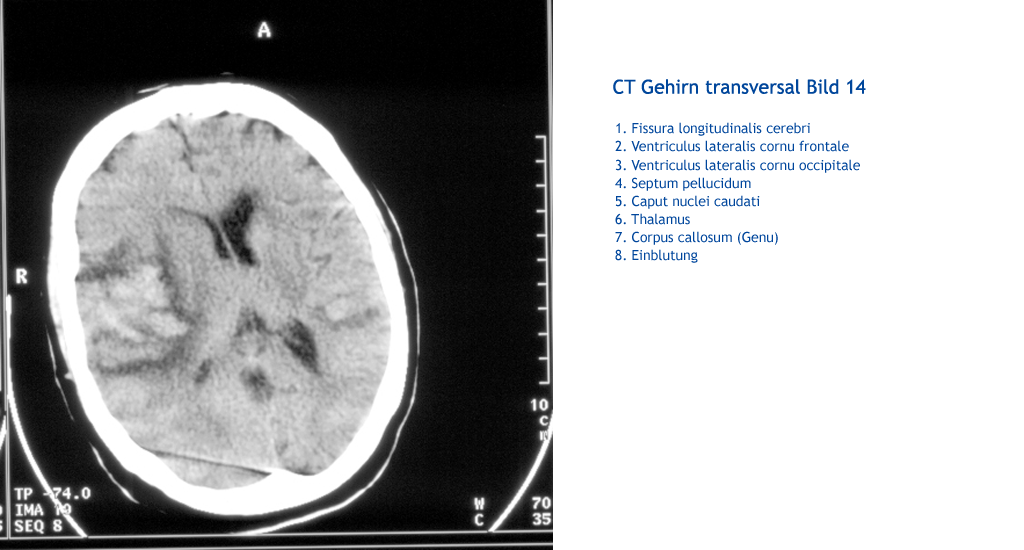

Einblutung Corpus callosum (Genu) Thalamus Caput nuclei caudati Septum pellucidum Ventriculus lateralis cornu occipitale Ventriculus lateralis cornu frontale Fissura longitudinalis cerebri